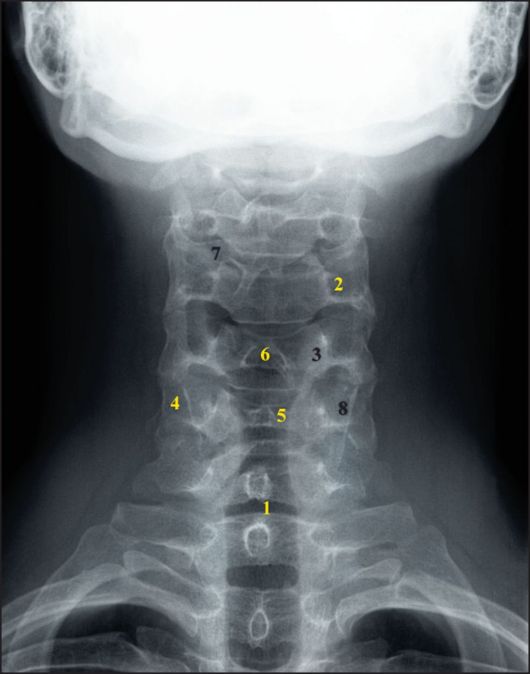

Медицинские снимки: рентген позвоночника сбоку